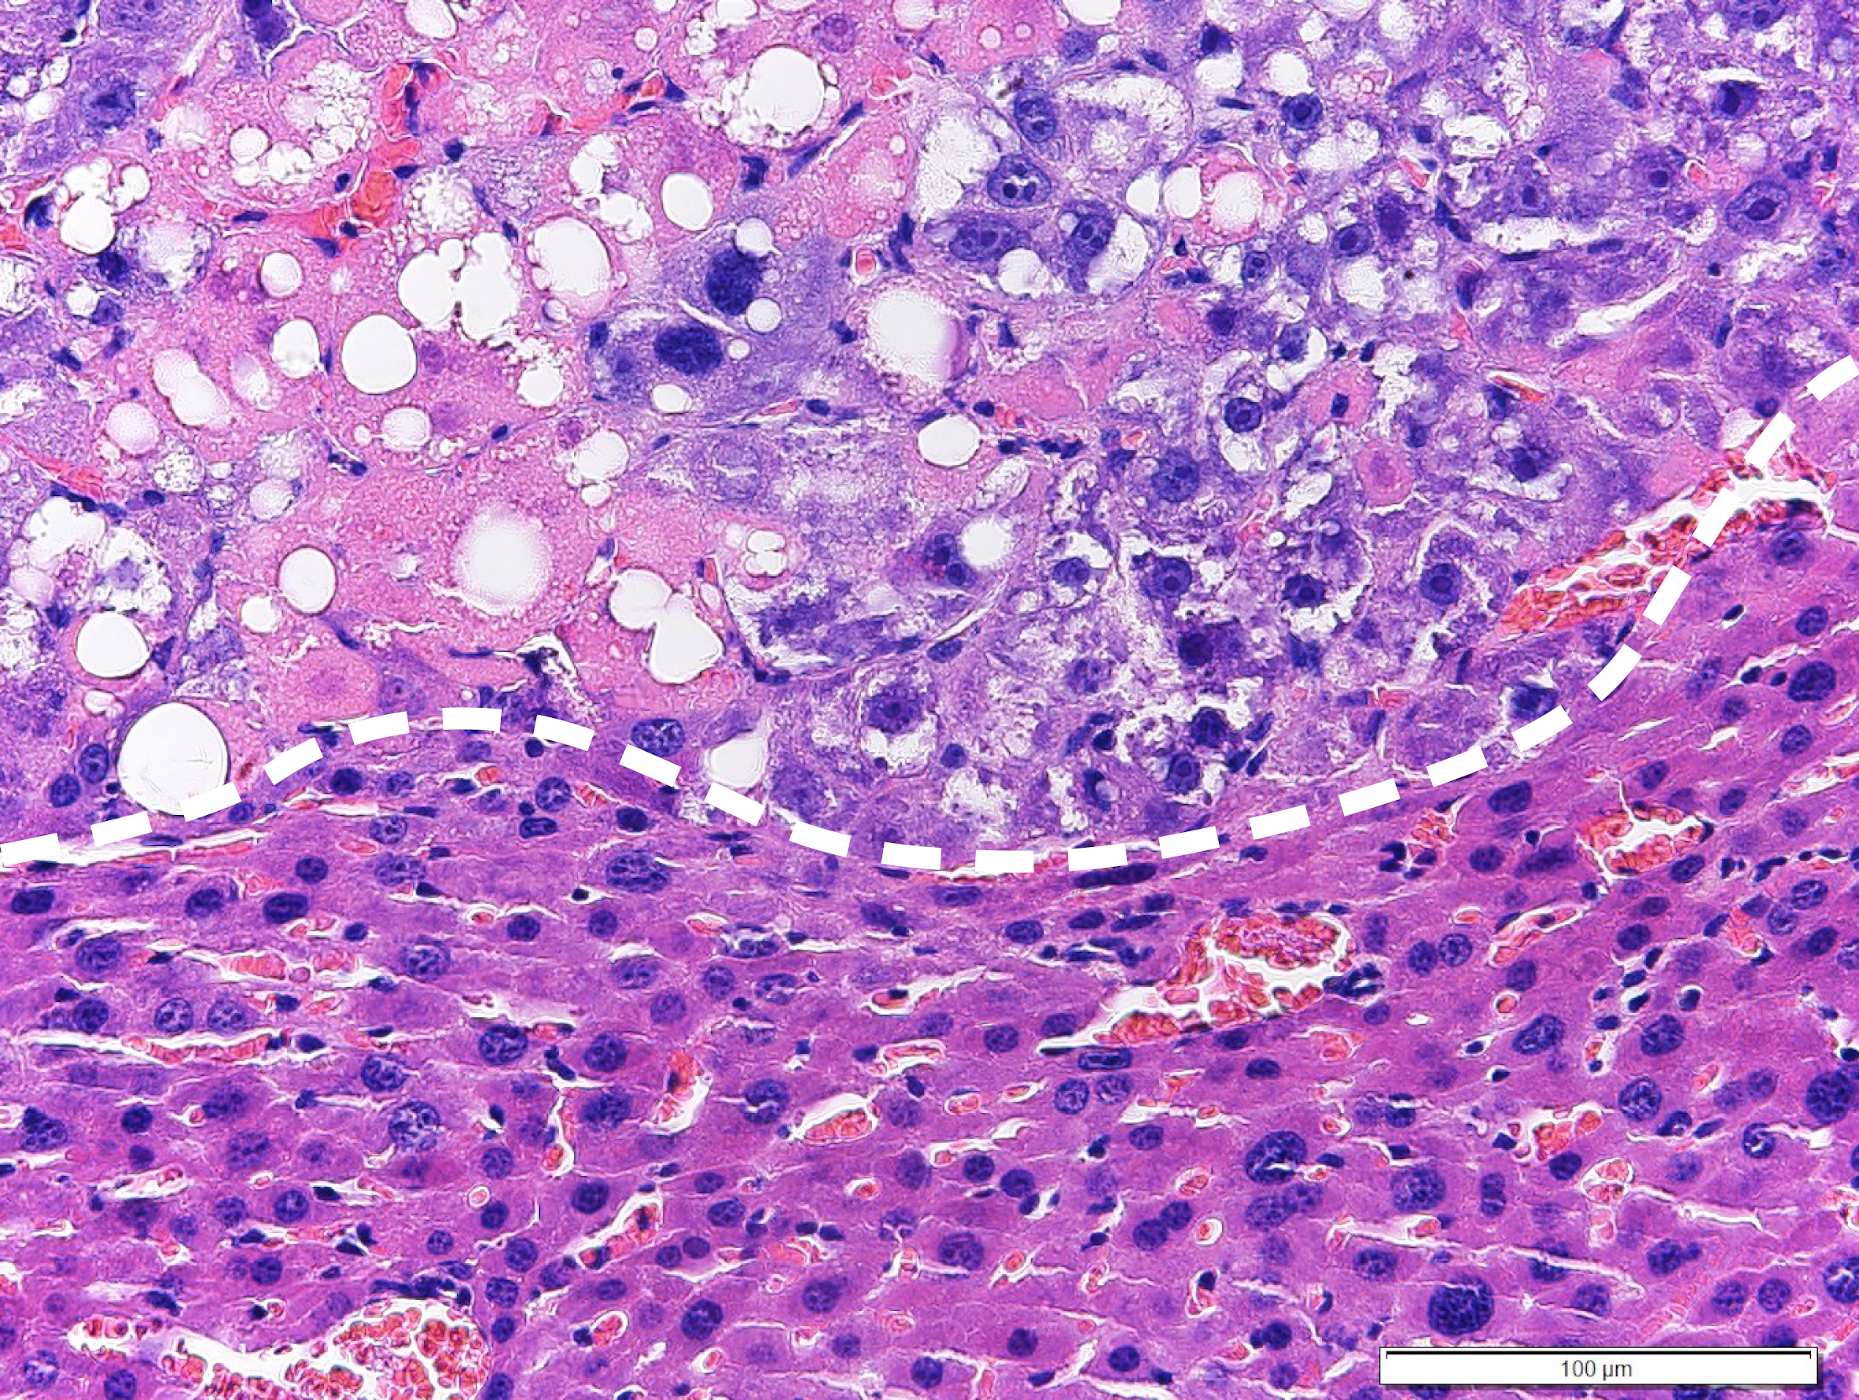

The new approach involves therapeutic intervention in the lipid metabolism of tumor cells. Activation of the so-called LXRα protein leads to an increase in fatty acid synthesis. Initially, this can be tolerated by the tumor cell, because saturated fatty acids (also known as bad fatty acids in nutritional medicine) are continuously converted to unsaturated (good) fatty acids by the enzyme stearoyl-CoA desaturase-1 (SCD1).

However, if a second protein, the so-called Raf-1 kinase, is inhibited at the same time, saturated fatty acids accumulate in the tumor cell, which cannot be tolerated by the tumor cell and leads to cell death of the tumor cell. Of particular importance is the fact that the new therapeutic concept has a strong efficacy against liver cancer, which is caused by fatty liver disease (NASH). Clinical trials have shown that these so-called NASH-HCCs are difficult to control with currently available targeted therapies or immunotherapies.